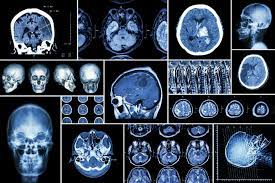

Our Medical Imaging department is responsible for offering services , Computed Tomography (CT), Echocardiography, Fluoroscopy, General Radiography, Magnetic Resonance Imaging (MRI), Mammography and Ultrasound.

Medical imaging refers to several different technologies that are used to view the human body in order to diagnose, monitor, or treat medical conditions. Each type of technology gives different information about the area of the body being studied or treated, related to possible disease, injury, or the effectiveness of medical treatment.